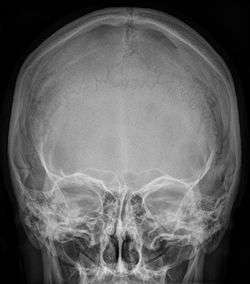

![]() Radiograph of the skull showing an interparietal bone between the occiput and parietal bones | |

An interparietal bone (os interparietale or Inca bone or os Inca. Var.[1]) is a dermal bone situated between the parietal and supraoccipital.

In humans, it corresponds to the upper portion of the squama of the occipital bone that lies superior to the highest nuchal line and is completely fused to the supraoccipital. However, in some individuals this portion remains separate from the rest of the occipital bone throughout life. In such cases, this separate bone is particularly referred as Inca bone. Inca bones in humans were first found in the skulls of contemporary indigenous peoples of the southern Andes as well as in those of mummies of the Inca civilization. Although the Inca bone was originally encountered as a variation in South American and Latin American cranial remains, the variation occurs in people from all geographic regions of the world and is by no means indicative of South/Latin American origin.